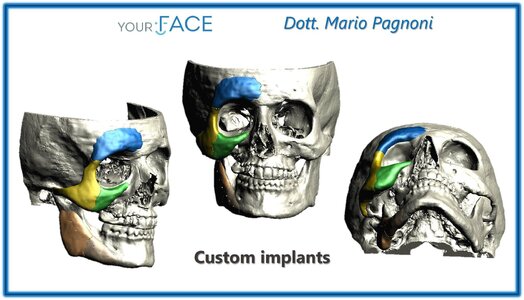

I’m 22 years old self-made multimillionaire with LTN-MTN face white guy with brown eyes brown hair. These are the surgeries that I need. 174cm, narrow frame (whatever). The face surgeries have the chance to shoot me into HTN territory.

3 years of pain, hundreds of thousands of dollars, and years spent living in geo-minned locations near world renowned doctors in Europe… face surgeries is about 1.5 years.

I’m 22 years old self-made multimillionaire with LTN-MTN face white guy with brown eyes brown hair. These are the surgeries that I need. 174cm, narrow frame (whatever). The face surgeries have the chance to shoot me into HTN territory.

3 years of pain, hundreds of thousands of dollars, and years spent living in geo-minned locations near world renowned doctors in Europe… face surgeries is about 1.5 years.